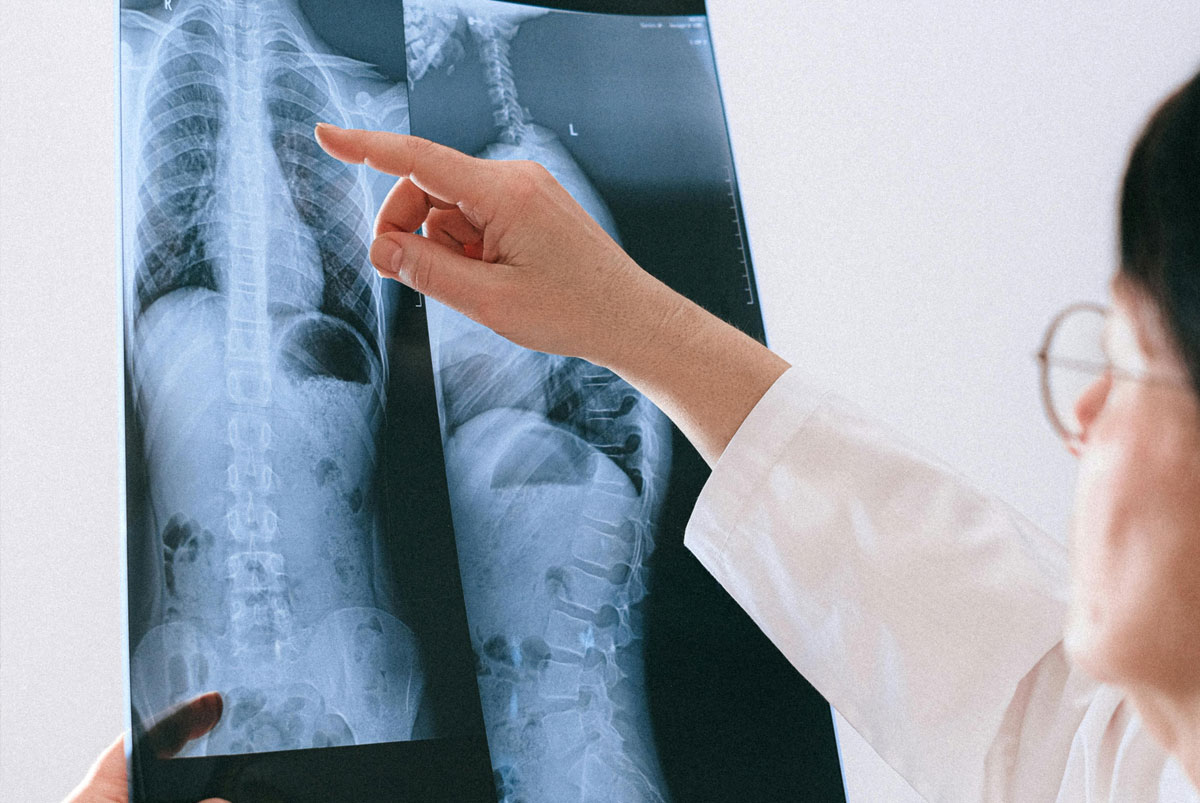

Spinal injuries are among the most serious types of personal injury and can have a profound effect on mobility independence and quality of life. Injuries to the spine or spinal cord may result in long-term pain nerve damage or permanent disability.

Spinal injuries can range from soft tissue damage and disc injuries to spinal cord damage causing partial or complete paralysis.

Evidence includes hospital records imaging reports and specialist spinal assessments. Financial evidence may include proof of income care costs equipment needs and future treatment estimates.